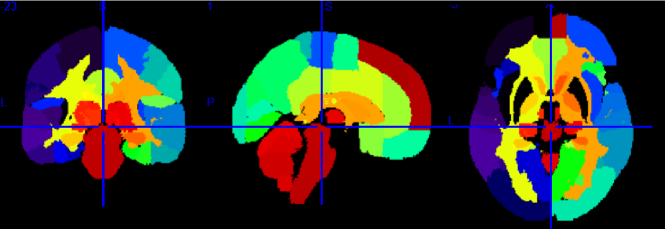

We explore genomewide associations with brain volume difference in terms of voxels; we also perform the same analysis based on groups of voxels, which is the focus of this work. This region of interests (ROIs) approach is a type of dimensionality reduction method that allows for information on local neighborhoods of voxels to be pooled, and reduces possible noise that associates with performing analysis using the entire brain voxels, we denote this as the region-wide study. In order to conduct the experiment using 119 ROIs, we extracted voxels from each brain region, and computed the average Jacobian scores (per region) that make up the 119 different brain regions from the GSK CIC Atlas as shown in Fig. 1, which is based on the Harvard-Oxford atlas with a 6-level hierarchy. To extract the corresponding voxels from each brain region in the atlas, we used the FLIRT linear registration tool from FSL (Jenkinson and Smith (2001), Jenkinson et al. (2002), Smith et al. (2004), and Woolrich et al. (2009)) in order to register the brain atlas to our template scan. This allows us to extract voxels of different brain regions from the subject’s scan and the registered atlas by direct comparison. We then used the average per-region Jacobian scores from each of the 119 ROIs as the response into genomewide association.